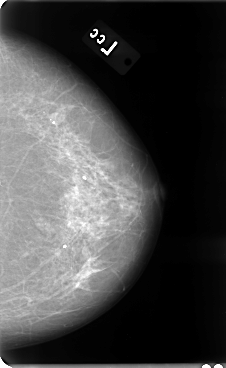

B_3075_1.LEFT_CC

LEFT_CC LINES 4776 PIXELS_PER_LINE 2936 BITS_PER_PIXEL 12 RESOLUTION 50 NON_OVERLAY

LEFT_MLO LINES 4760 PIXELS_PER_LINE 2792 BITS_PER_PIXEL 12 RESOLUTION 50 NON_OVERLAY